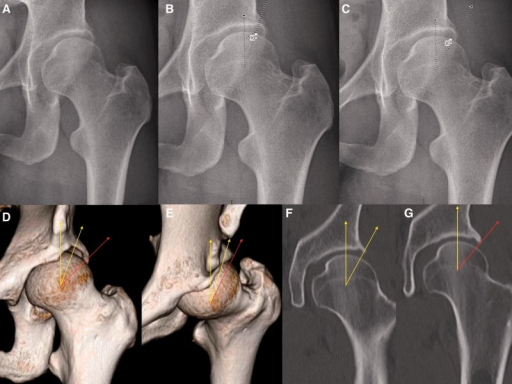

AP pelvis radiograph of an 18-month-old showing left hip developmental dysplasia. The acetabular index measures 38 degrees (normal <30 degrees at this age). Shenton's line is disrupted. The femoral head is subluxed with inadequate coverage. The center-edge angle is negative. The sourcil is oblique. There is delayed ossification of the left femoral head ossific nucleus compared to the right. This represents late-presenting DDH requiring surgical intervention.

Describe the radiographic findings and relevant measurements.